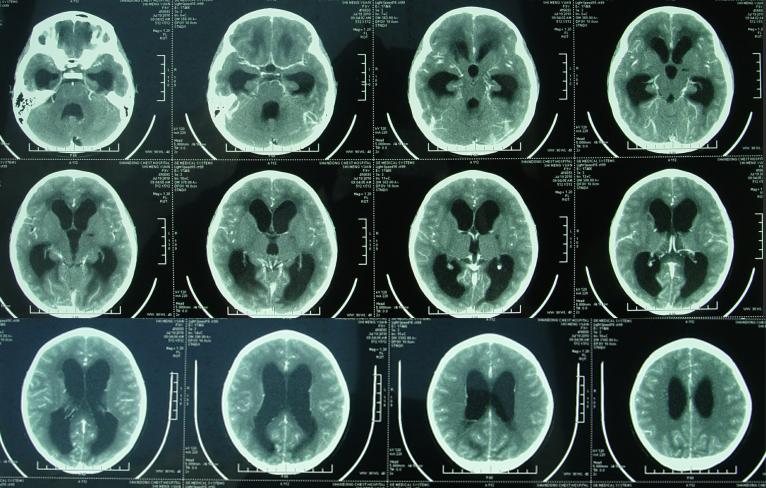

在住院治疗1个月零9天的时候即在2010年7月19日,再次复查头颅CT,结果显示脑积水又有所加重(图-4)。此后病情比较稳定,平均每周呕吐一次,头痛偶然需要临时加用甘露醇处理。

图-4:2010年7月19日头颅增强CT

在继续治疗20余天之后即在2010年8月31日,再次查头颅CT增强(图-5)虽仍有脑积水的表现,查肺片示稍有感染(图-6)。但腰穿检查,具有蛋白和白细胞数均接近正常但颅压仍高达300mmH2O以上的结果,虽仍经常出现癫痫发作,以抗癫痫药物控制;但医生仍建议出院观察。

图-5:2010年8月31日头颅增强CT